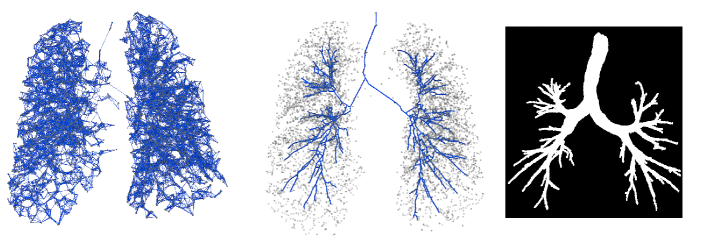

Refer to caption

Fig. 3: Input graph derived from a chest scan depicting the initial connectivity based on 𝐀insubscript𝐀in{\mathbf{A}}_{\text{in}} between nodes (left). Nodes of the input graph (grey dots) overlaid with connections derived from the reference adjacency matrix, 𝐀rsubscript𝐀𝑟{\mathbf{A}}_{r} (center). Binary volume segmentation obtained from the reference adjacency matrix and the corresponding node features (right). Note that due to visualisation artifacts introduced by viewing 3-d image projected into 2-d the nodes and the edges might not be very clear.

Reference adjacency matrices are obtained from the reference segmentations using the preprocessing procedure described in Section 3.1.1. The extracted nodes and edges that are inside the corresponding reference segmentations are connected using a minimum spanning tree algorithm to obtain a single connected tree, yielding reference adjacency matrices that are used for training both the GNN and MFN models. A sample input graph along with the connections based on the reference adjacency matrix is shown in Figure 3 (center) .

The output of graph refinement models yields connectivity information about the airway centerlines. For evaluation purposes, we convert the predicted subgraph into a binary segmentation. This is done by drawing binary voxels within a tubular region that interpolates the radii of the nodes, along edges given by 𝐀=𝕀[(𝜶>0.5)(𝜶T>0.5)]𝐀𝕀delimited-[]𝜶0.5superscript𝜶𝑇0.5{\mathbf{A}}={\mathbb{I}}[({\boldsymbol{{{\alpha}}}}>0.5)\land({\boldsymbol{{{\alpha}}}}^{T}>0.5)]. One such binary segmentation is visualised in Figure 3 (right).